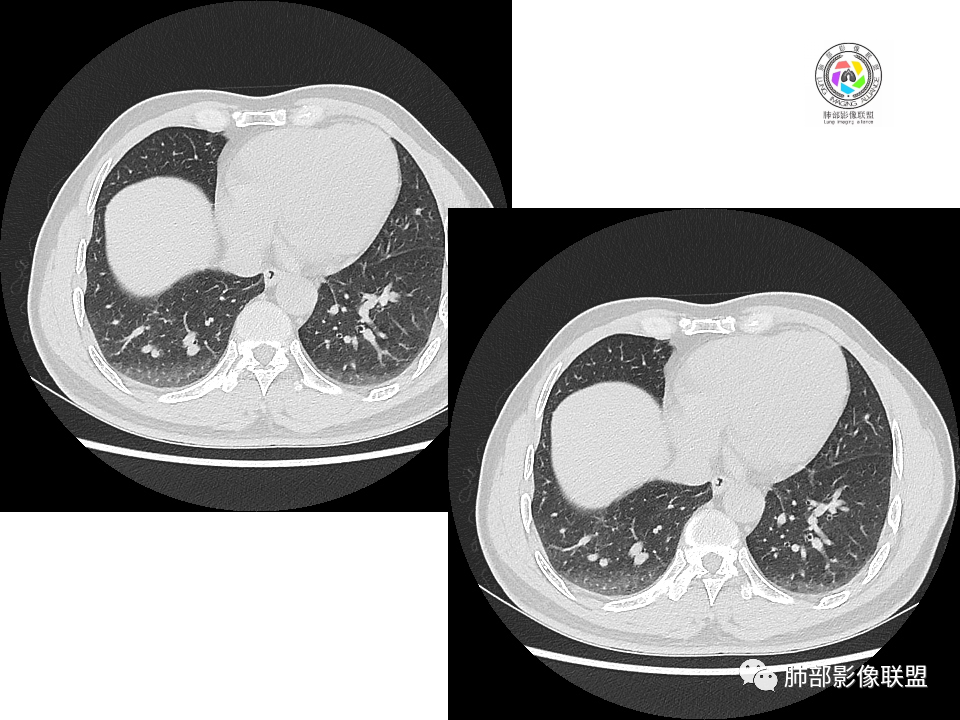

血管也是稍推移,在边缘,病灶密度均匀,边缘稍收缩;均匀强化;

这两个病灶的密度、强化、形态、边缘、与血管的关系类似;还是一元论吧。

2.右肺下叶背段胸膜下块影,边界清楚光整,上下极见磨玻璃晕,未见明显分叶毛刺和棘状突起,未见胸膜凹陷或胸壁侵入。密度均匀,轻度不均匀强化。未见支气管进入。

1.边缘光整干净,大病灶缺乏坏死等,不符合鳞癌影像学特征。尽管有吸烟史,还是偏年轻。

2.边缘光整,会是小细胞癌或是大细胞癌吗?小细胞癌的肺门纵隔淋巴结增大往往十分夸张,该患者不符合。

注意,基底段支气管血管束旁的小结节影,即便是淋巴结,也与背段病灶引流途径不符。

3.会是转移瘤吗?如前所述,患者偏年轻,缺乏相关原发肿瘤病史,强化程度不高,似乎也缺乏支持点。

4.良性占位绕不过去,如发生于该部位的孤立性纤维瘤等……

病灶不均匀强化可以将含液支气管囊肿排除在外。

5.慢性感染灶。缺乏临床表现,强化不显著会想到继发性肺结核,背段病灶过于光整均匀,周边过于干净使人狐疑,且“成掎角之势”的中叶病灶结核灶特点也着实不多。

有老师分析,多发病灶有磨玻璃晕,可以符合隐球菌感染,确实如此。但背段边缘如此锐利的块影还是更容易让人联想到新生物。